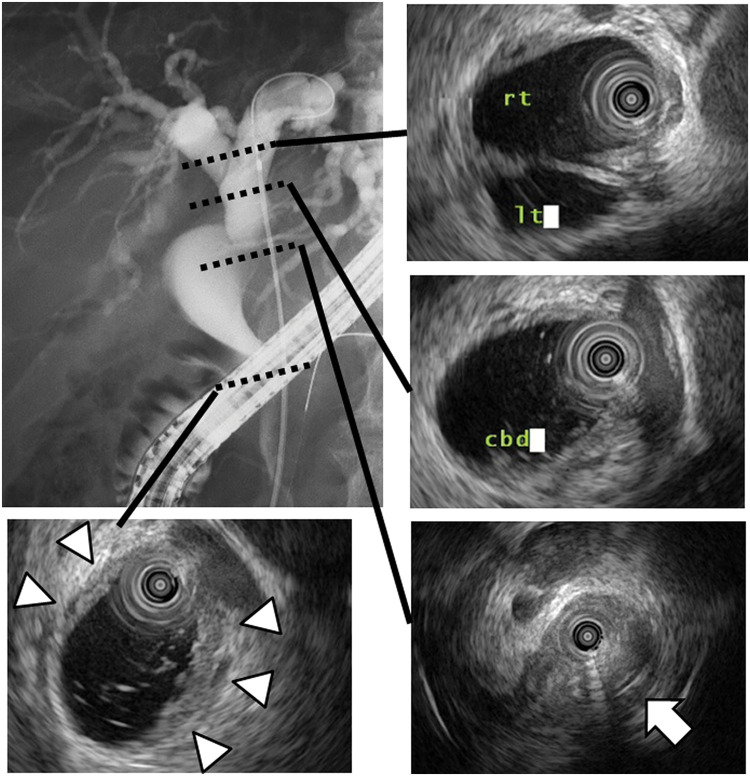

Case presentation: A 77-year-old man presented to our hospital with general fatigue and jaundice. He had previously undergone an open cholecystectomy and lithotomy for gallbladder cancer and common bile duct stones 19 years earlier. Blood tests revealed elevated levels of hepatobiliary enzymes and tumor markers. Both computed tomography and magnetic resonance imaging indicated dilatation of the intrahepatic and common bile ducts, and an enhanced nodule was observed in the common hepatic duct. Intraductal ultrasonography identified a papillary tumor infiltrating the distal bile duct from the common hepatic duct. Brush cytology subsequently helped confirm adenocarcinoma. Consequently, the patient was diagnosed with Bismuth type 1 perihilar cholangiocarcinoma and underwent subtotal stomach-preserving pancreaticoduodenectomy. Histological examination revealed the tumor as pancreatobiliary-type ICPN associated with invasive carcinoma, which had originated in the remnant cystic duct and invaded the common hepatic duct. A retrospective review of the resected gallbladder specimens from 19 years earlier confirmed ICPN according to the current classification, establishing this as a metachronous occurrence of ICPN.